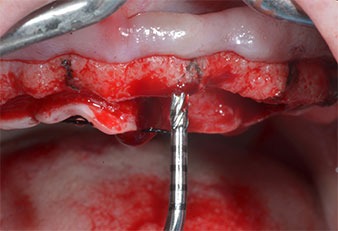

Para marcar las posiciones del implante y realizar la preparación piloto, se utilizó un inserto piezoeléctrico (Piezomed I1) con revestimiento de diamante y forma de llama (figura 3). Se tomaron precauciones para realizar movimientos hacia arriba y hacia abajo, con una potencia reducida, una irrigación completa y una baja presión (por debajo de 300 g). A continuación, se aplicó un inserto piloto (Piezomed I2A/I2P) para aumentar el diámetro inicial de 2 mm de los sitios de implante (figura 4), seguido de un inserto de 3 mm (Fig. 5).

Motor de implantes (Implantmed)

Fig. 5: El diámetro final se logró con los insertos Piezomed I3A/I3P. En el caso de los implantes de 10 mm de las posiciones 11 y 21, los sitios se finalizaron con una fresa rotatoria de 3,5 mm en un motor de implantes (Implantmed).

Insertos Piezomed

Fig. 4: El siguiente paso fue el aumento piloto con los insertos I2A/I2P, que se aplicaron con un movimiento rotatorio horizontal.